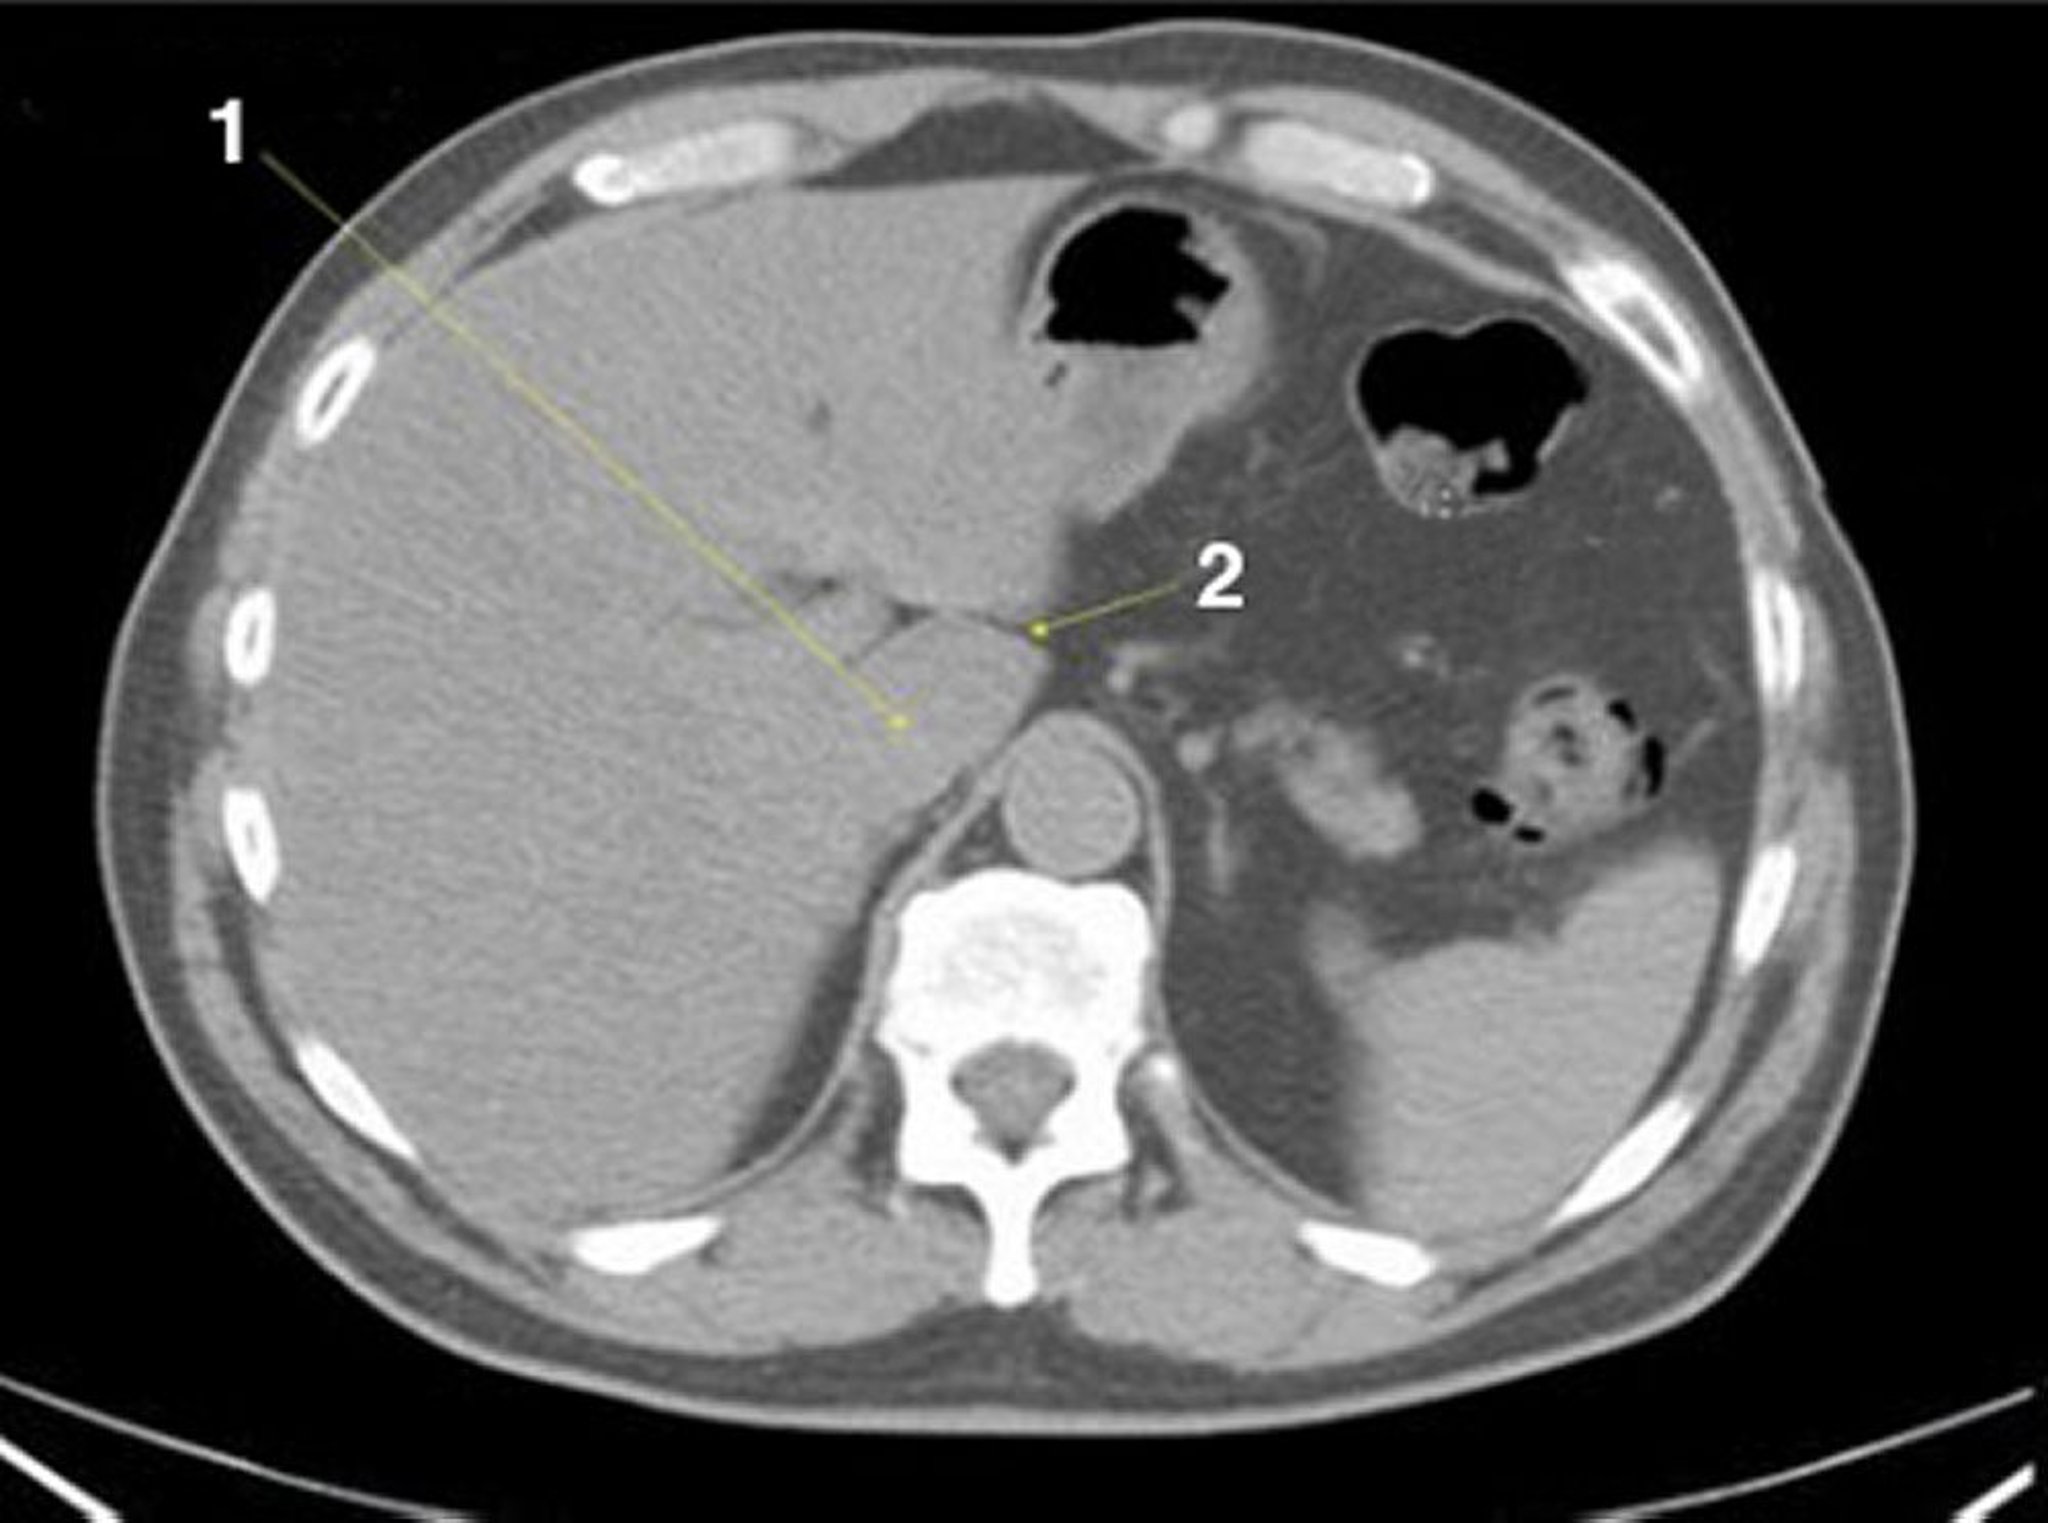

Phim chụp CT vùng bụng và vùng chậu không thuốc cản quang cho thấy giải phẫu bình thường (lát cắt 4)

1 = thùy đuôi của gan; 2 = khe của dây chằng tĩnh mạch.